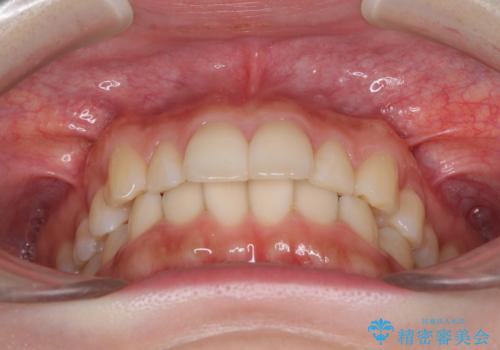

- 上の前歯が出っ張っている気がするとのことで来院された患者様です。

半年もせずにインビザラインを全く使用することができなくなってしまったので、治療開始から1年ほどでワイヤー矯正へ変更することとなりました。

ワイヤー矯正へ変更してからはあっという間に治療が進み、1年弱で終えることができました。